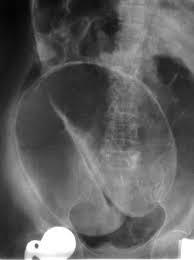

Barium enema of “lead pipe colon”

Loss of haustral marking characteristic of UC

Apple core colon

Characteristic of colorectal carcinoma